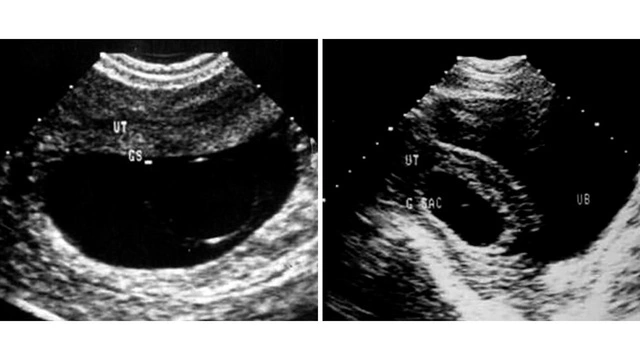

При замершей беременности диагноз ставят (или подтверждают, если выкидыш уже начался) по результатам УЗИ. Исследование может показать анэмбрионию или гибель плода. Между этими ситуациями есть разница:

- Анэмбриония — это патология, при которой внутри плодного яйца нет эмбриона, он не был сформирован или перестал расти до пятой недели.

- Гибель плода — нарушение, при котором эмбрион сначала формировался нормально, но затем перестал расти⁴.

Если эмбрион погиб на раннем сроке, при ультразвуковом исследовании будут видны сгустки, его фрагменты. Если на УЗИ видно пустое плодное яйцо, это не всегда является анэмбрионией — иногда так же выглядит нормальный плод на очень раннем сроке.

Пузырный занос

Пузырный занос — нарушение во время беременности, при котором плод погибает. Патология развивается, если в оплодотворении участвует яйцеклетка без гаплоидного ядра или сразу два сперматозоида. Состав хромосомного набора при пузырном заносе оказывается нарушенным. В норме оболочка плода (хорион) имеет ворсинки, с помощью которых она прикрепляется к эпителию матки. При пузырном заносе на месте ворсинок образуются пузырьки, заполненные жидкостью (рис. 1). Если при этом ткани эмбриона отсутствуют, пузырный занос называют полным. Если эмбрион или ткани эмбриона частично сформированы, пузырный занос является неполным.